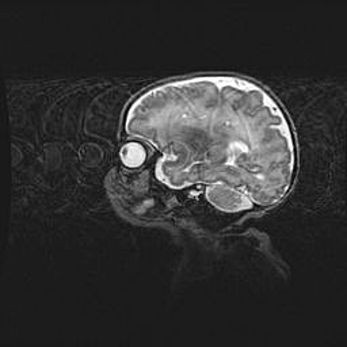

Аномалия Денди-Уокера. Признаки гипоплазии мозолистого тела.

Возраст: 5 месяцев 3 дня

Вес: 5550 г

Пол: мужской

Окружность головы: 39 см

Срок гестации: 40 недель

Аномалия Денди-Уокера – это порок развития головного мозга, для которого характерна триада симптомов: гипотрофия или аплазия червя мозжечка и/или полушарий мозжечка, расширение четвёртого желудочка с формированием ликворной кисты задней черепной ямки, гипертензионная гидроцефалия различной степени.

Гипоплазия мозолистого тела относится к дефектам внутриутробного этапа развития мозговой ткани, возникающим в процессе закладки структур головного мозга, что происходит на начальных этапах развития эмбриона.